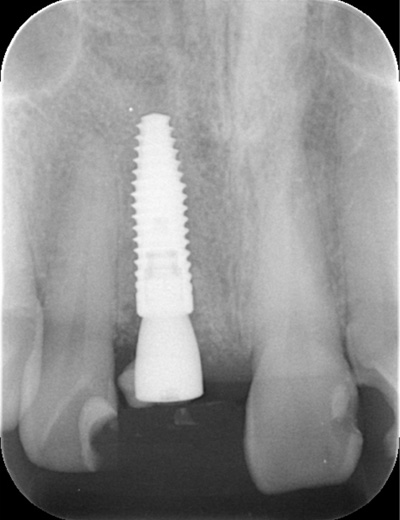

| 年代・性別 | 50代 男性 |

|---|---|

| 主訴 | 右下の歯がないのでインプラントをして欲しい |

| 治療期間 | 約6ヶ月 |

| 費用 | 600,000円 |

| 治療内容 | インプラント、骨造成、結合組織移植、セラミック修復 |

| 治療に伴うリスク | インプラント周囲炎 セラミックの破折、脱離 |